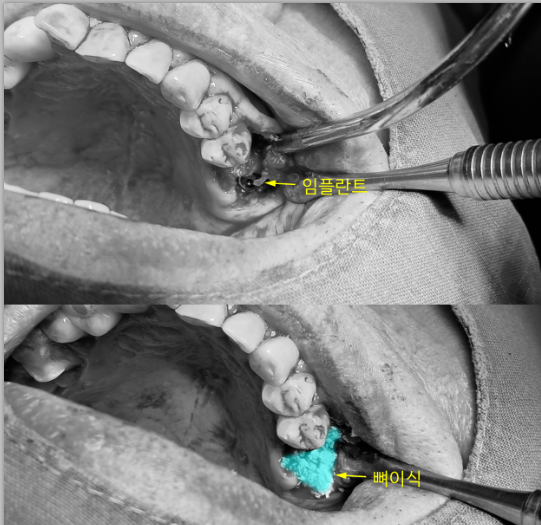

4) 수술 과정 요약

국소마취 하에 발치를 진행한 뒤, 상악동 바닥을 안전하게 거상해 임플란트가 자리 잡을 수 있는 수직 공간을 만들었습니다. 이후 이식재를 이용해 결손 부위를 보강하고, 같은 날 임플란트를 식립했습니다.

수술 중에는 초기 고정(Primary stability) 여부와 잔존골 형태를 확인하면서 단계별로 진행했습니다.